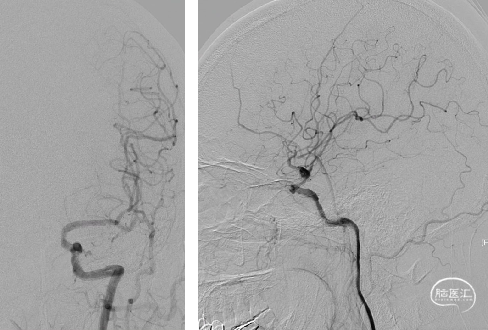

术后3月余复查:

动脉瘤愈合,支架内血流通畅。